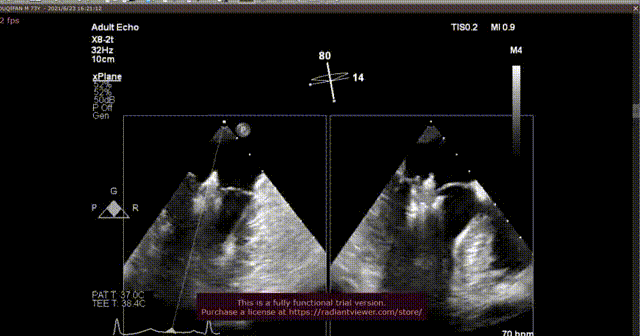

谢明星教授进行术中食道超声监控与引导

此款二尖瓣夹合器不同于市面上已上市的Mitra Clip,其结构设计与整体功能更加简化。手术采用股静脉穿刺送入导丝建立通路,房间隔穿刺将二尖瓣夹合器送入左房,在3D食道超声与DSA引导下通过独特的可调弯导管进行二尖瓣脱垂瓣叶的捕获、夹合与释放。

本次手术由心外科尚小珂教授、陈澍教授,心内科钟禹成教授,超声科谢明星教授李贺教授共同完成,法国波尔多里尔大学Thomas Modine教授远程指导。术后即刻超声心动图评估返流降至轻度,夹合器锚定良好、器械顺利撤出体外,手术取得圆满成功。术后第二天超声心动图评估返流为轻度,夹合器稳定。术后尚小珂教授表示:“经皮二尖瓣夹合器的应用成功,给大量无法耐受传统开胸手术的患者提供新的希望,微创介入术式必定会被越来越多的患者接受。本器械最大的优势在于其结构设计简单易上手,学习曲线短且效果显著,不仅针对退行性二尖瓣病变,对于心衰功能性二尖瓣反流一样可达到治疗效果。迄今为止,武汉协和医院仍然是华中唯一可以同时开展四个瓣膜介入手术的中心。

术后即刻超声

术后2D超声